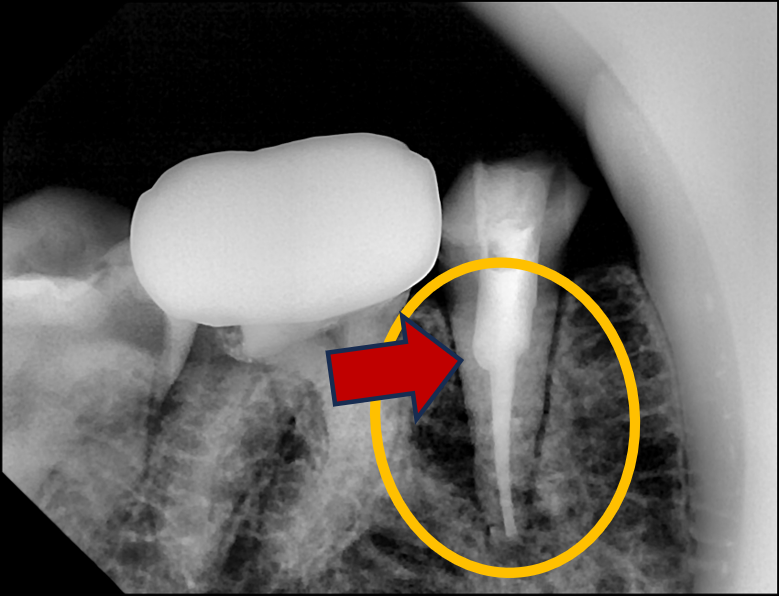

Root - zx 로 뿌리끝 싸인을 확인 후, 다시 엑스레이.

재신경치료를 위해 파이버 포스트를 제거하고 근단부의 끝까지 접근한 엑스레이 사진

흐아~~ 다행히 포스트를 제거하고 뿌리끝에 접근하는 데에 성공했다!!

솔직히 말하면, 운이 좋았다고도 할 수 있다.

만약 왼쪽으로 2~3mm만 더 들어가서 엑스레이를 찍었다면... ㄷㄷㄷ

이런 운의 요소를 줄이려면, 수시로 PA 엑스레이를 찍어가면서 확인해야 하는데,

좌-우 축이 아니라, 전-후 축은 이마저도 확인이 안 되므로,

느낌이 싸하다면 중간에 CT도 찍어봐야 하는데 그마저도 제한적이다.

아무튼 중간에 4장의 엑스레이를 찍어가며, 무사히 포스트 제거에 성공.

파이버 포스트 제거 후 재신경치료를 완료하고 근관을 충전한 사진